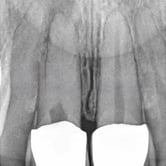

Reabsorción Interna

La reabsorción interna es la destrucción progresiva de la dentina desde el interior del diente hacia afuera, generalmente debido a un trauma o inflamación pulpar.

Los pacientes pueden notar un cambio de color en el diente.

Es necesario un tratamiento de conducto para detener el proceso y salvar el diente. Sin tratamiento, el diente puede debilitarse y fracturarse.